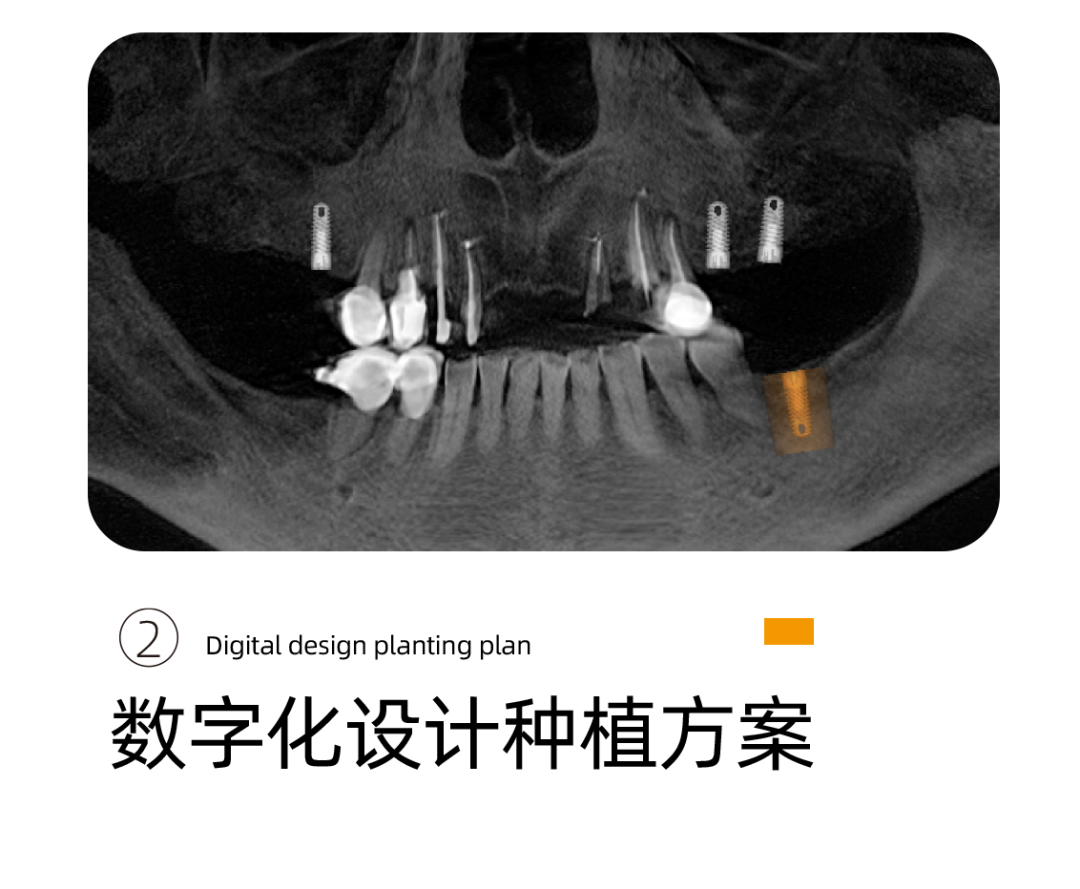

针对阿姨的情况,李雪松院长为阿姨指定全套的数字化种植方案。

什么是UNIC数字化种植方案呢?

其实就是借助Sirona CBCT全景影像信息和相关修复信息为基础,借助数字化专业种植设计软件进行术前诊断和种植方案规划。

通过数字化种植手术导向模板,将术前制订的种植方案准确应用于种植手术和即刻修复的全过程,实现以修复为导向的牙种植修复。

全数字化导板设计会依靠自身数字化的精确定位和微创特点,大大减少失误操作,提高种植手术的精准度。